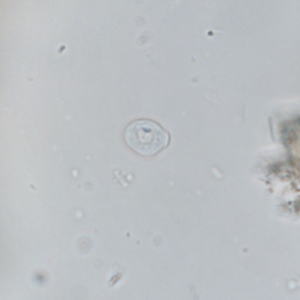

Les kystes de Chilomastix mesnili sont piriformes et de petite taille (6 à 10 μm), à paroi fine et réfringente. Ils présentent un noyau ainsi qu’un organite juxtanucléaire (cytostome) où se loge le flagelle; néanmoins cette structure est difficilement visualisable (Garcia, 2021). Le contenu du kyste est davantage visualisé lors de l’utilisation d’hématoxyline ferrique.

Le diagnostic différentiel comprend les autres kystes de protozoaires (notamment de petits kystes de flagellés et amibes). La distinction se fait sur la morphologie des noyaux, leur nombre, et la taille du kyste (Garcia, 2021). Une coloration à l’hématoxyline ferrique peut être utile pour visualiser les détails cytoplasmiques. Une coproculture permet de faire évoluer les kystes en trophozoïtes et d’améliorer le diagnostic.